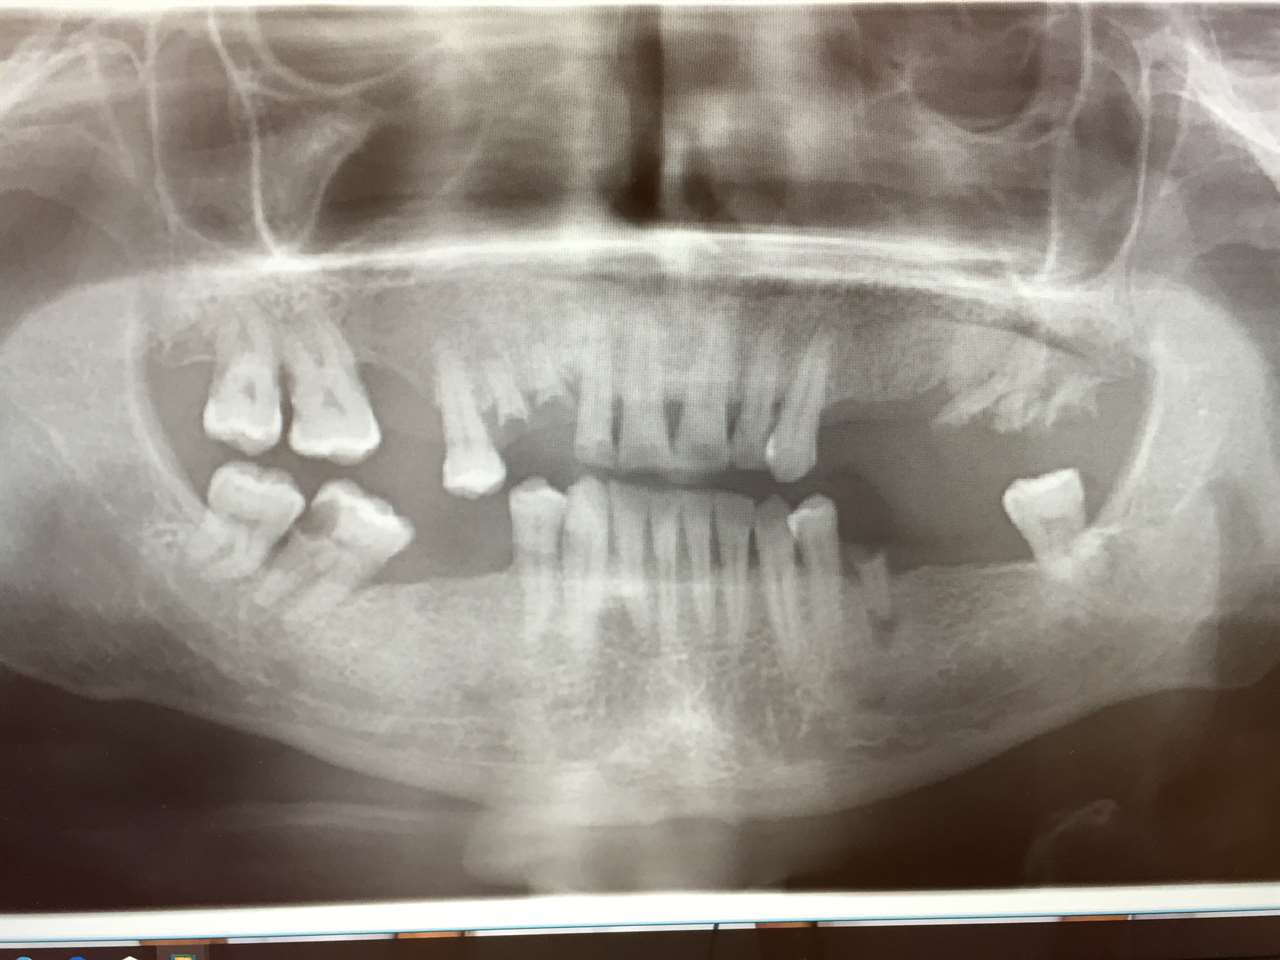

Alsó állcsont teljes rehabilitációja 72 óra alatt, azonnal terhelhető implantátumokkal súlyos paradontitisben szenvedő dohányzó páciens esetében. Az alsó állcsont fogai mind mozogtak az előrehaladott fogágypusztulás miatt.

A fogakat eltávolítottuk, a gyulladt, fertőzött csontot kitakarítottuk, kifertőtlenítettük, majd azonnal implantáltunk.

Svájci, IHDE márkájú, azonnal terhelhető implantátumokat helyzetünk be, és ezekre harmadnapra rögzített, hosszútávú, fémvázas, esztétikus műanyaggal leplezett hidat ragasztottunk be.

Ezt az ideiglenes hidat a sebek gyógyulása miatt használjuk, de tartóssága miatt véglegesként is használható.

A legtöbb esetben, ahogy itt is, 6 hónap múlva porcelán hídra cseréljük, a teljes gyógyulás után.